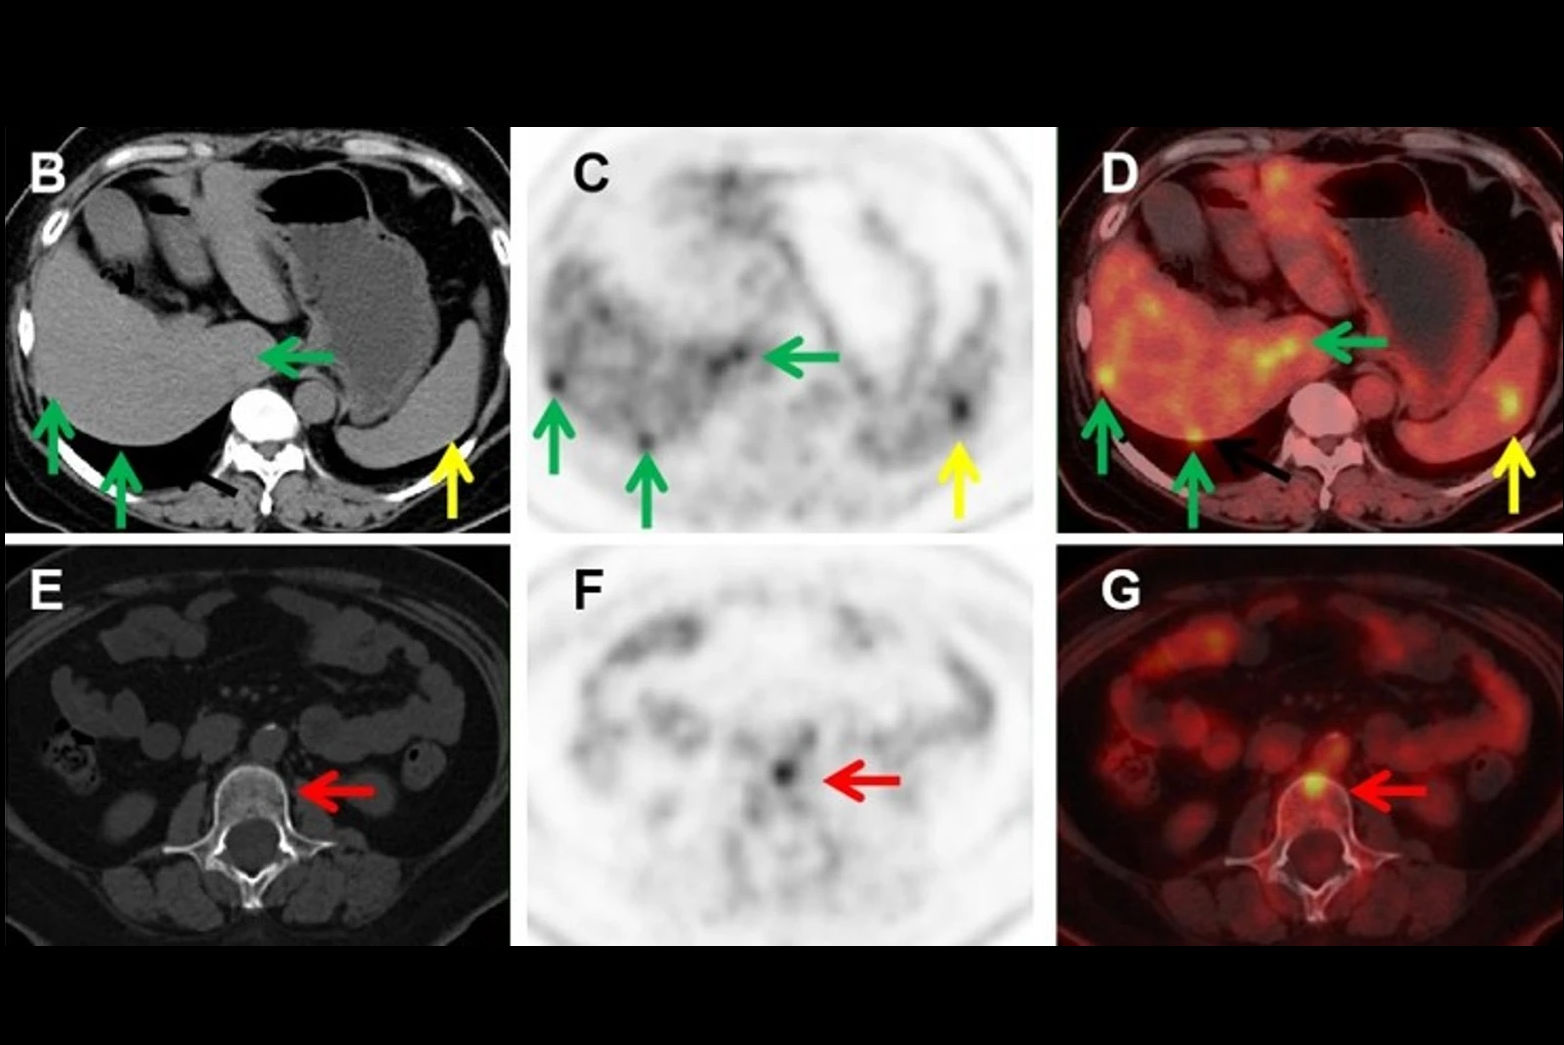

Representative PET/CT fusion axial view of the sinus of one convalescent animal (CM2) with the corresponding quantification (b, c) of the mean and maximum Zr-89 COVA1-27-DFO PET signal in the brain of all animals normalized to that at day 1 post-injection. (d) Representative CT lung lesion, indicated by the yellow circle, and its associated PET signal (e), indicated by the white circle, on day 7 post injection. (f) Corresponding quantification of the maximum PET signal in the lesional (gray background, n = 6 areas) and nonlesional areas (square symbols, white background, n = 6 areas) on day 7 post injection compared with that for naïve animals (black symbols (n = 7 areas). (g) Axial view of the Zr-89 COVA1-27-DFO PET signal in the brain, indicated by the white arrows, at day 3 post injection. Corresponding quantification (h, i) of the maximum and mean Zr-89 COVA1-27-DFO PET signal in the brains of all animals normalized against that on day 1 post injection. Mann Whitney two-sided t-test, *: p = 0.014, **: p = 0.008. Convalescent + COVA animals are indicated in green and the mock + COVA animals in black. Data are presented as individual values and the associated mean and SD. Source data are provided as a Source data file. Image and caption available for republishing under Creative Commons license (CC BY 4.0 DEED, Attribution 4.0 International) and courtesy of Nature Communications.

The group detected Zr-89 COVA1-27-DFO uptake by the lungs of one convalescent animal, along with CT ground-glass opacity. Tracer uptake on PET/CT was higher in lung lesion regions than in nonlesion lung areas, and significantly higher than in uninfected animals, according to the findings.

In addition, the researchers found a visible PET signal in certain regions of the brains of both convalescent animals, with much higher maximum standard uptake values than in uninfected animals (ratios of 0.8 and 0.63 vs. 0.43 and 0.48).